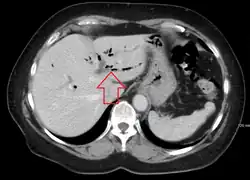

| CT scan of pneumobilia |

Pneumobilia is the presence of gas in the biliary system. It is typically detected by ultrasound or a radiographic imaging exam, such as CT, or MRI. It is a common finding in patients that have recently undergone biliary surgery or endoscopic biliary procedure. While the presence of air within biliary system is not harmful, this finding may alternatively suggest a pathological process, such as a biliary-enteric anastomosis, an infection of the biliary system, an incompetent sphincter of Oddi, or spontaneous biliary-enteric fistula.